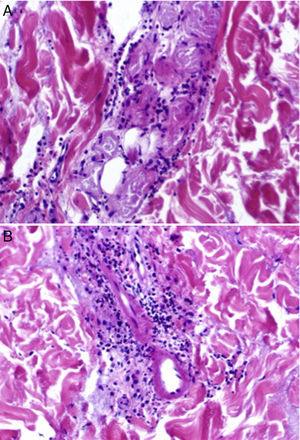

El estudio histopatológico mostró una ampolla subepidérmica con focos de reepitelización (fig. 2), así como focos de necrosis del epitelio glandular en los ovillos ecrinos, con infiltración periglandular neutrofílica (fig. 3A). Se observaron infiltrados dérmicos, perivasculares y perianexiales, de predominio neutrofílico, y focos de necrosis fibrinoide en la pared de pequeños capilares dérmicos con infiltración neutrofílica de esta (fig. 3B).

A) Focos de necrosis del epitelio glandular en los ovillos ecrinos con infiltración periglandular neutrofílica. Hematoxilina-eosina, ×20. B) Infiltrados dérmicos, tanto perivasculares como perianexiales, de predominio neutrofílico, y focos de necrosis fibrinoide en la pared de capilares dérmicos con infiltración neutrofílica de la misma. Hematoxilina-eosina, ×20.